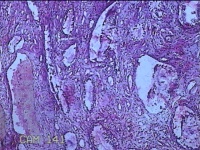

性别

女

年龄

44岁

临床诊断

宫颈赘生物

一般病史

发现宫颈赘生物2年余。

标本名称

宫颈组织

大体所见

灰白暗红色组织3.8x1.5x0.8cm一块,表面光滑,以宫颈12点缝线标记处切开,切面灰白粉红色,质软,宫颈3点处见灰白粉红色囊性肿物1.8x1.5x0.3cm一个,切开肿物,内见大量乳白色内容物,囊壁厚0.1cm。